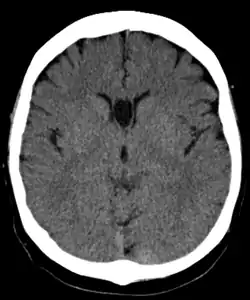

Полость прозрачной перегородки (лат. cavum septi pellucidi) — полость, находящаяся между листками прозрачной перегородки. Полость содержит ликвор, попадающий туда через поры в листках.[1]

Спереди полость ограничена коленом мозолистого тела; сверху — стволом мозолистого тела; сзади — передними ножками и столбами свода мозга; снизу — передней комиссурой и клювом мозолистого тела; латерально — листками прозрачной перегородки.[2]

В большинстве случаев полость не сообщается с полостью желудочковой системы мозга, что делает неправомочным её описание как «5-го желудочка» головного мозга, тем не менее, иногда её называют пятым желудочком.

Собственно полость прозрачной перегородки расположена на уровне основания передних рогов боковых желудочков мозга, а её распространение в заднем направлении в область тел боковых желудочков выделяют под названием полость Верге (лат. cavum vergae). Во время эмбрионального развития происходит закрытие полостей в задне-переднем направлении, из-за чего персистирование полости Верге при закрытой полости прозрачной перегородки встречается значительно реже.